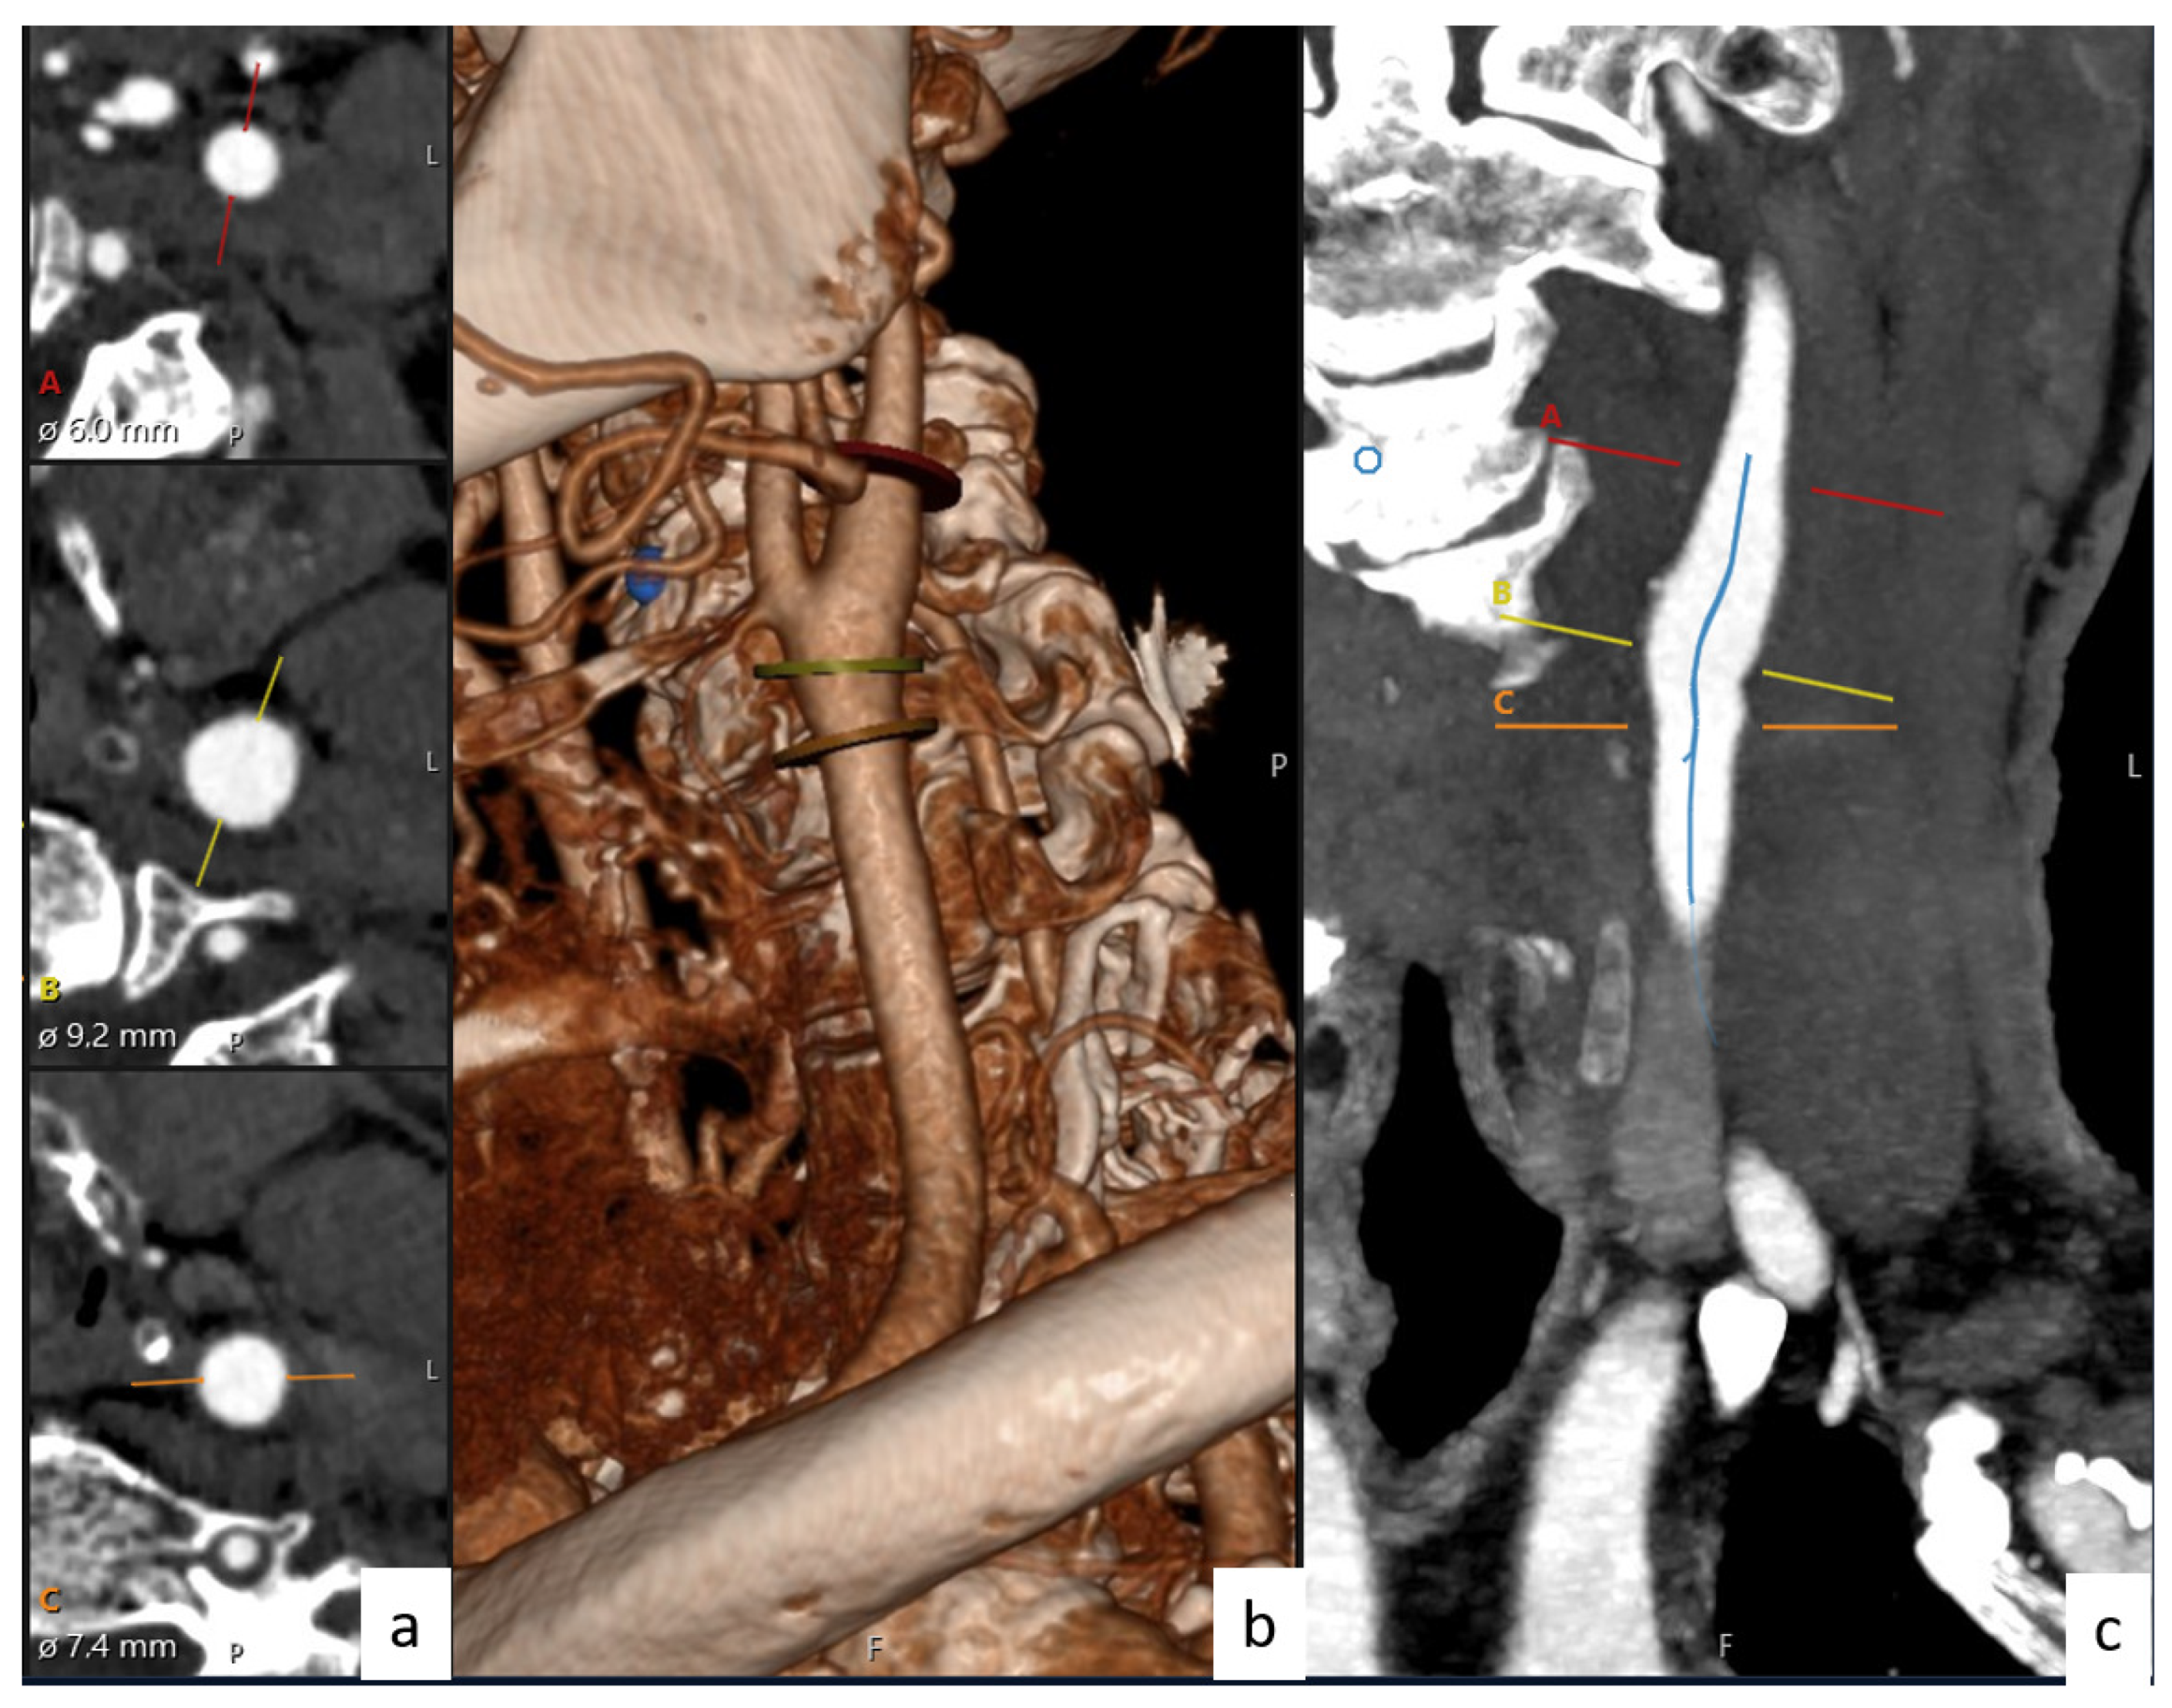

2.7. Data Collection

Figure 2. Diameters and angles of carotid artery with the help of Sectra software. (a) Diameter, (b) 3D imaging of carotid arteries, and (c) artery lumen centers.

Figure 3. Set of 3D images of the carotid arteries obtained with AW Server software for patients: (a) normal, (b) stenosis, (c) aneurysm, and (d) dissection.